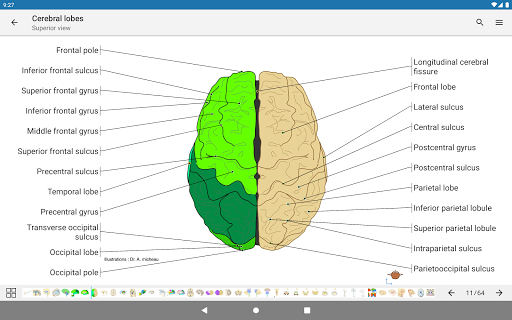

*Find your anatomical parts more easily thanks to the new, more intuitive and powerful search feature

- The anatomic view now displays more labels